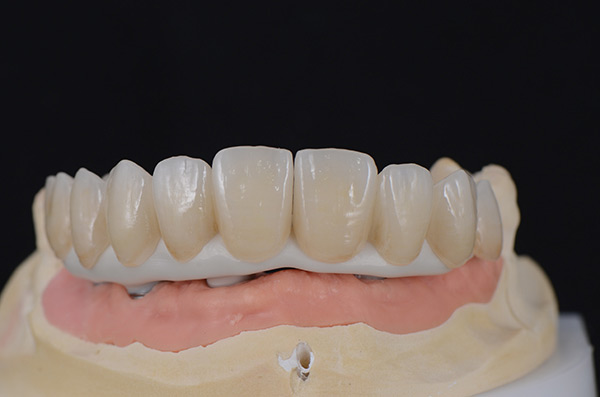

Fig 10. The full-arch zirconia framework with individual lithium-disilicate crowns, which were individually luted in the laboratory.

Figure 10